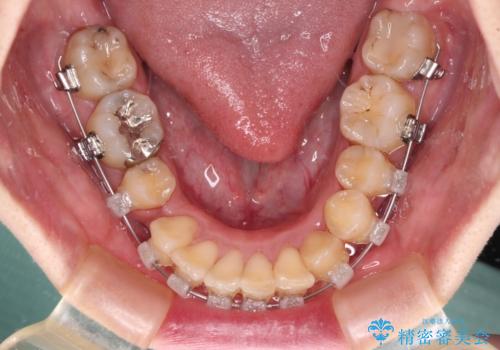

- クリアブラケット

- 3年4ヶ月

- 30回以上